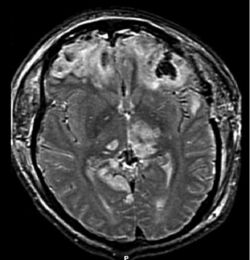

MRI scan showing damage due to brain herniation after TBI[2]